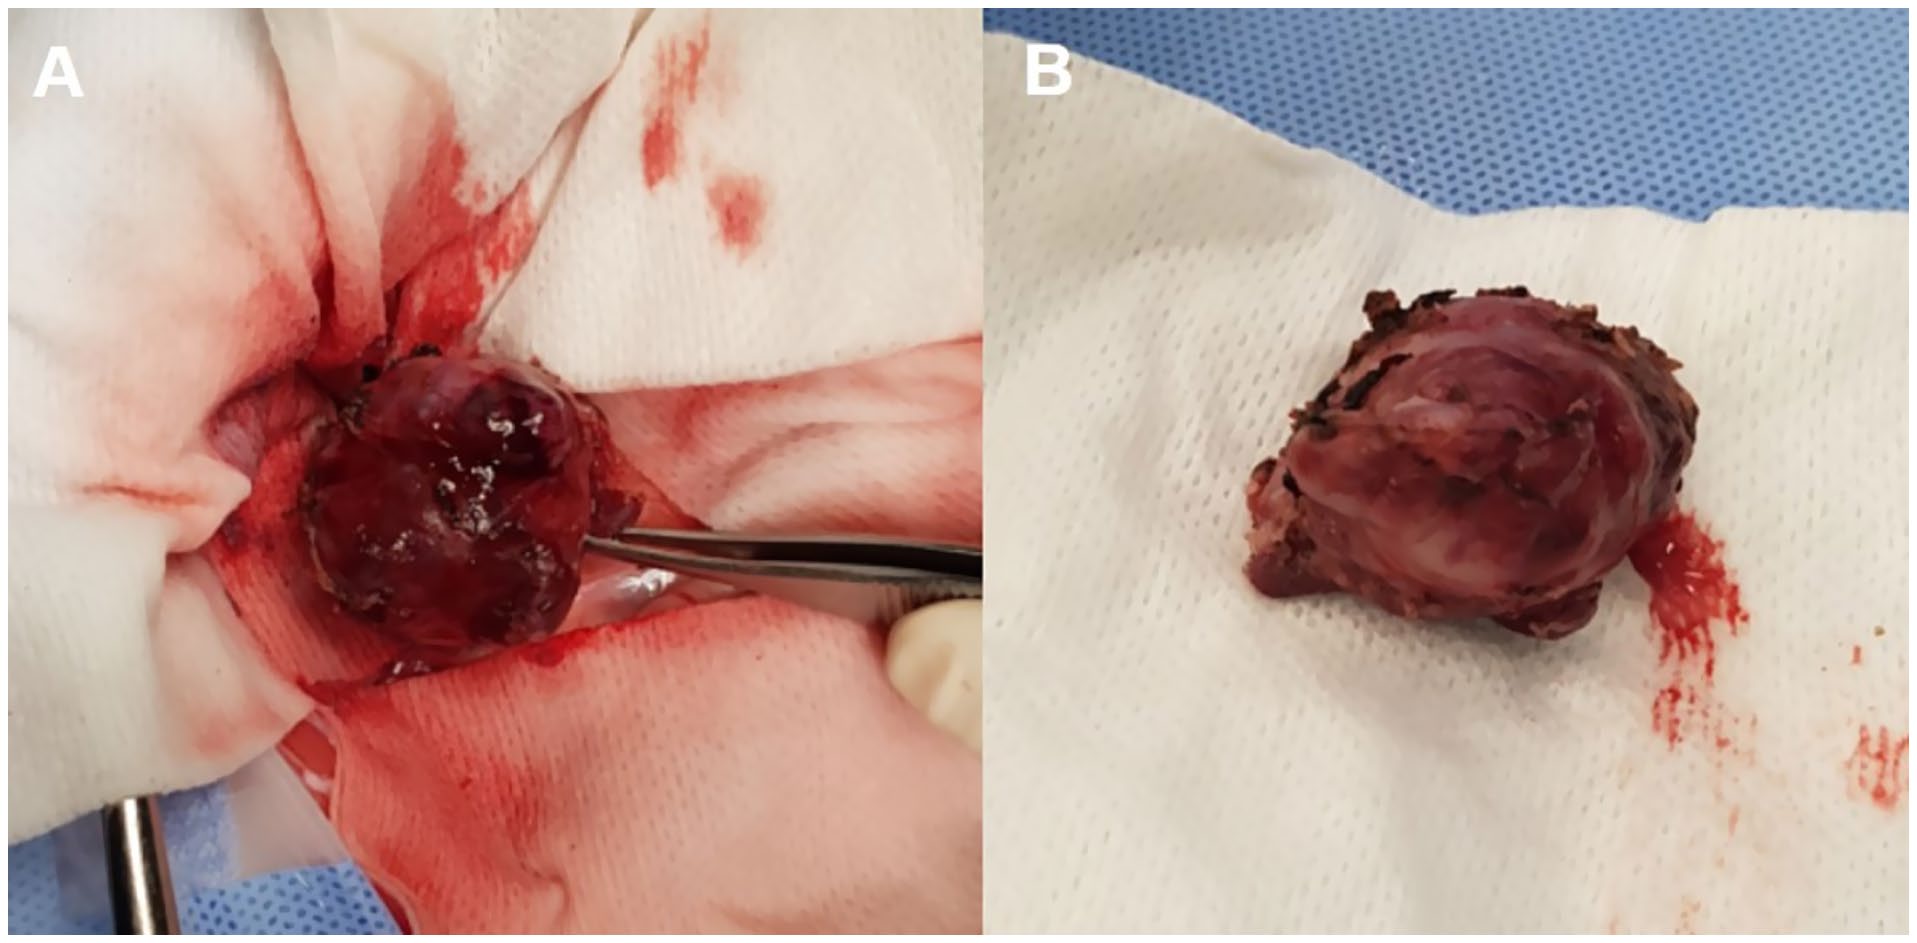

该不规则椭圆形肿块在未出现显著出血的情况下被切除(下图)。解剖分离在肾静脉和后腔静脉的背外侧完成。肿块连同其包膜被整体切除,但在紧邻两侧肾上腺的区域,切除未包括包膜。